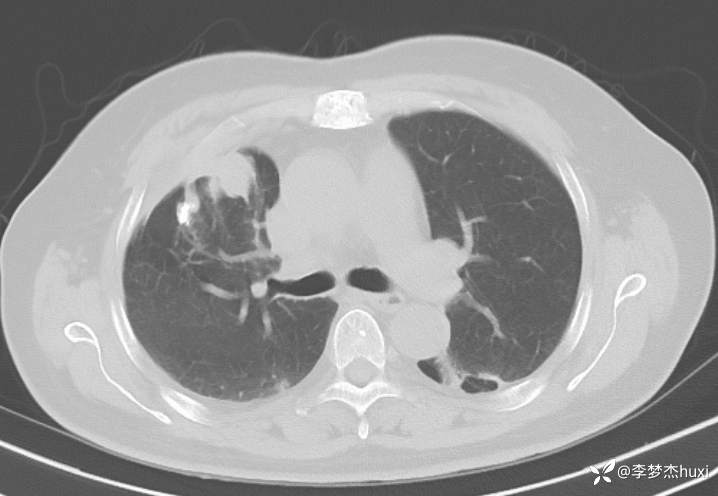

女性69岁,胸痛住院,检查发现肺占位性病变,猜病理

辅助检查:胸部CT:右肺占位?炎症?双肺炎性变,左肺下叶陈旧性病变,双肺纹理增多,主动脉及冠状动脉钙化,双侧胸膜局部增厚,胆囊结石,多发肝囊肿?请结合超声。

临床诊断:肺占位